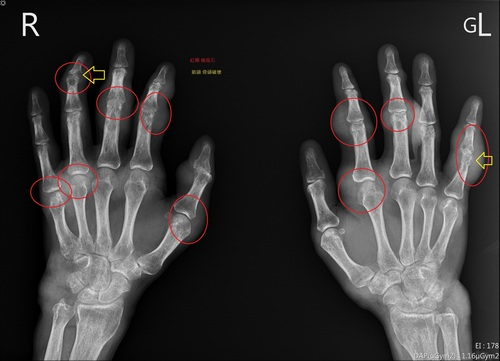

▲痛風患者手部X光片,紅圈為痛風石,黃色箭頭為遭破壞骨頭

痛風是一種急性的關節炎,症狀包括關節紅腫、發熱、劇烈疼痛,主要發生原因是尿酸結晶累積在關節,時間久了甚至引發急性痛風性關節炎、長痛風石,潘郁仁醫師說,痛風石通常是長在常發作的關節位置,包括手指、腳趾、膝蓋、手肘、腳踝,很多人發作時痛到無法行動要請假。